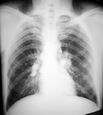

Vascular congestion (recognized as prominent pulmonary veins)

cephalisation.

Next, interstitial edema and increased lymph flow manifests itself as Kerley lines.

Next, basal congestion with smaller lungs due to increased elastic recoil. Congested, boggy Liver also pushes the diaphragm up.

Lastly, full-blown pulmonary edema: acute diffuse alveolar pattern